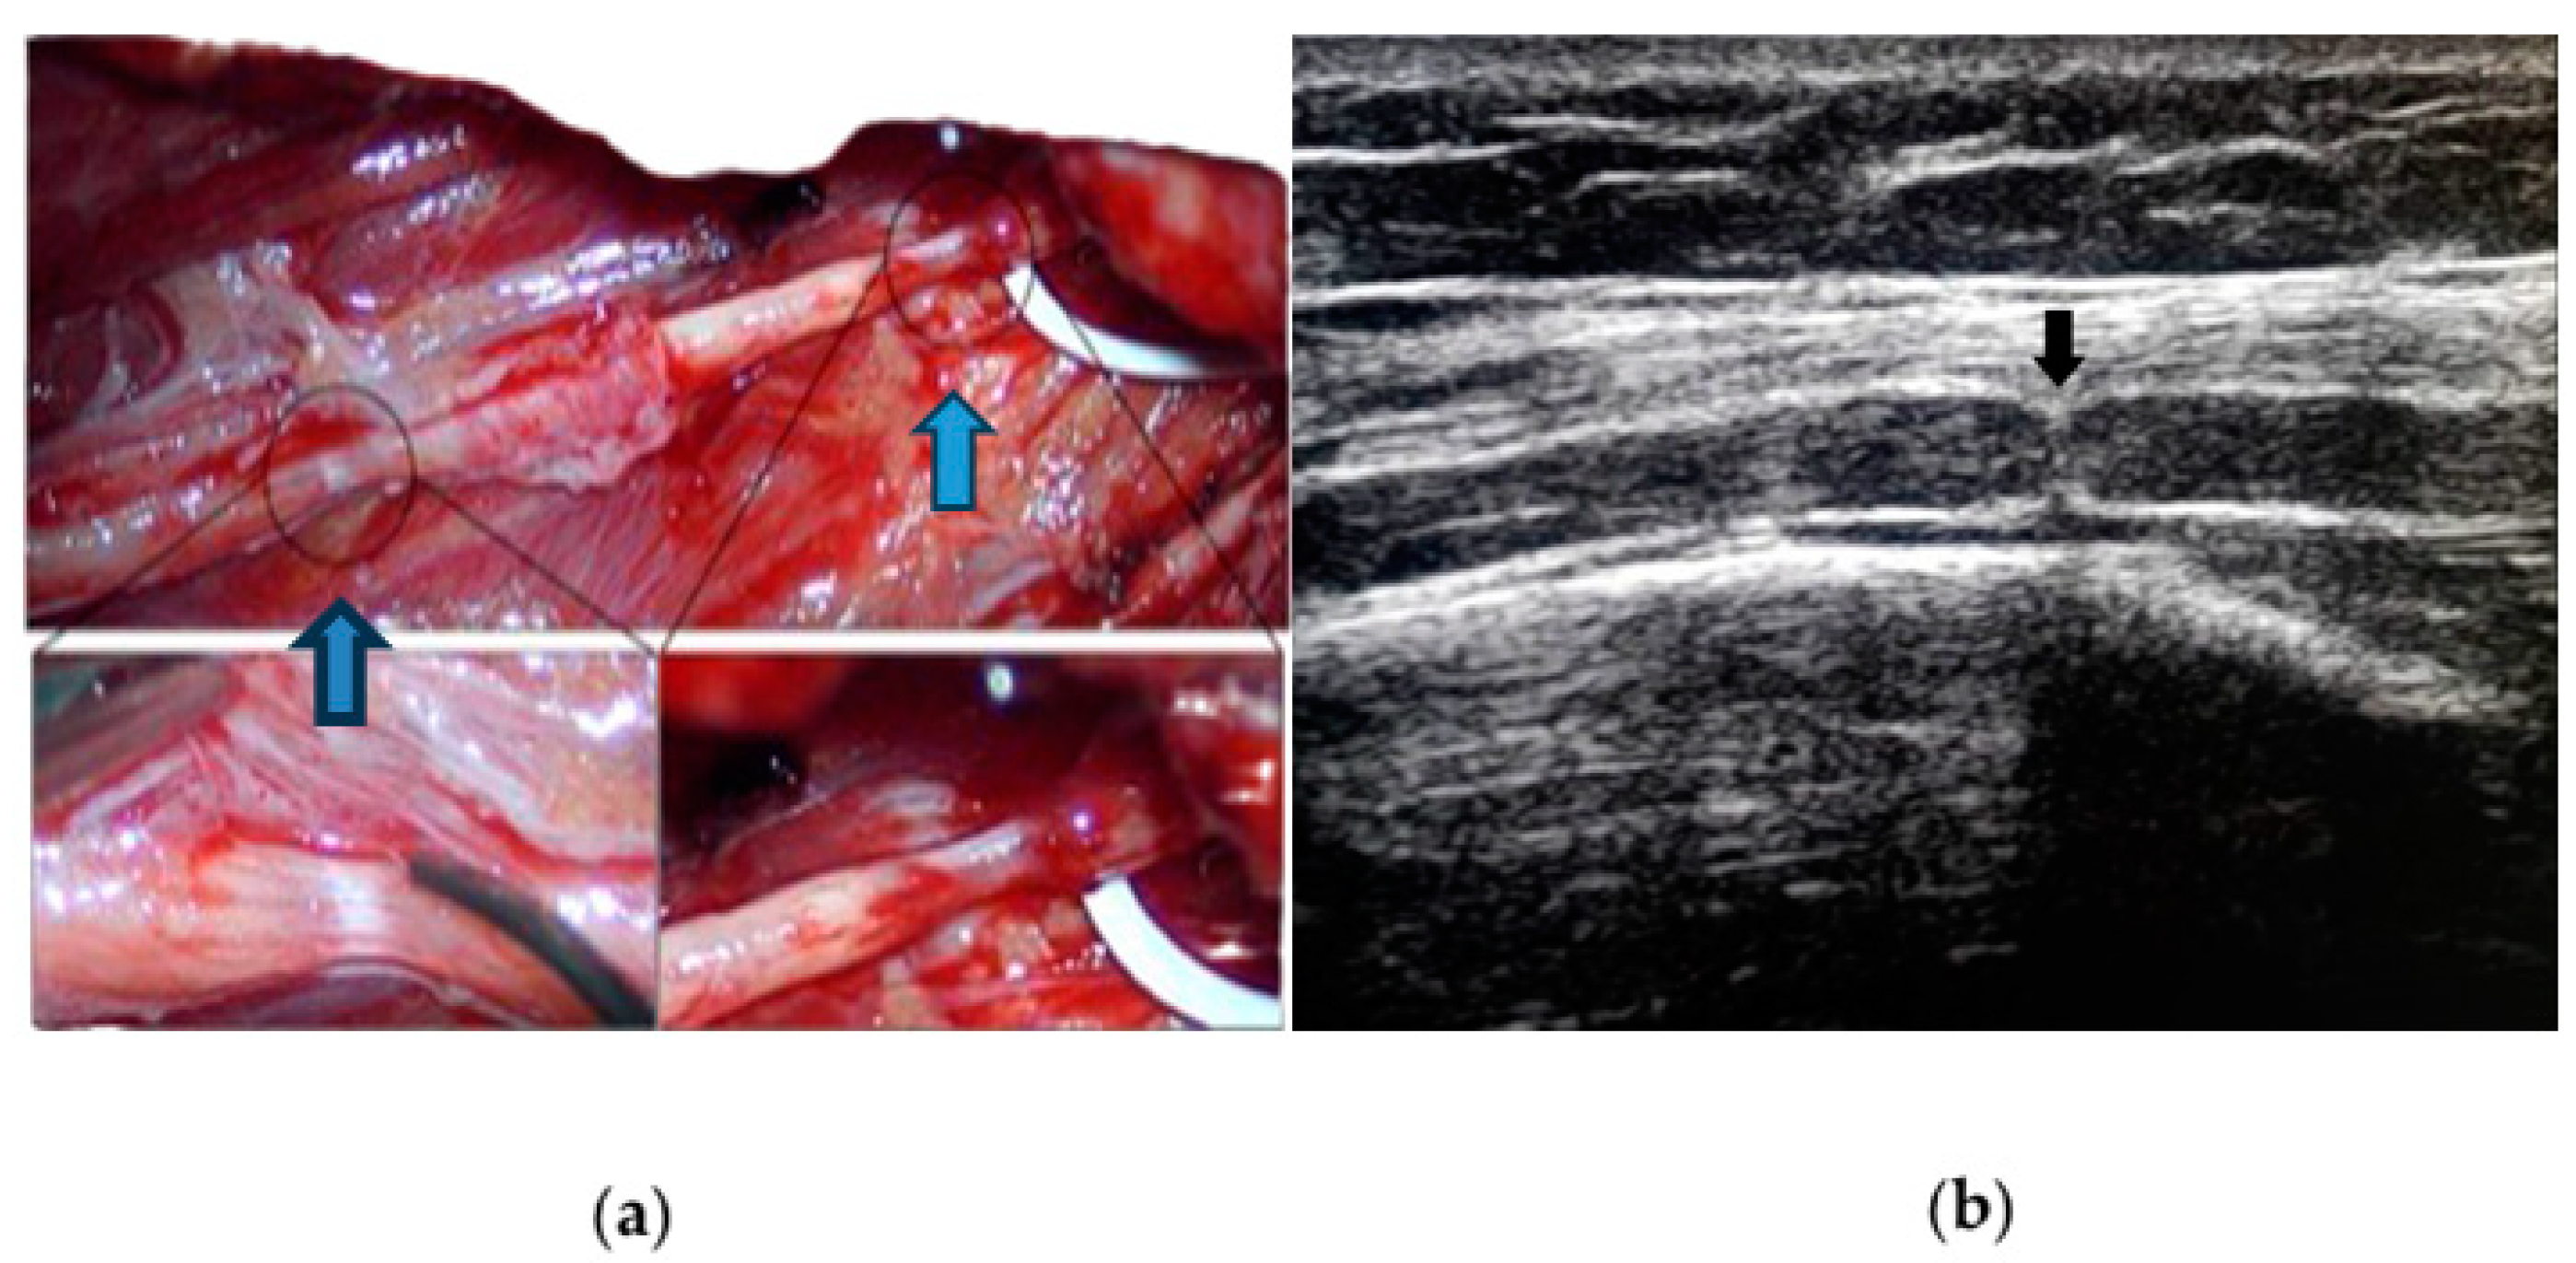

- (a)

- (b)